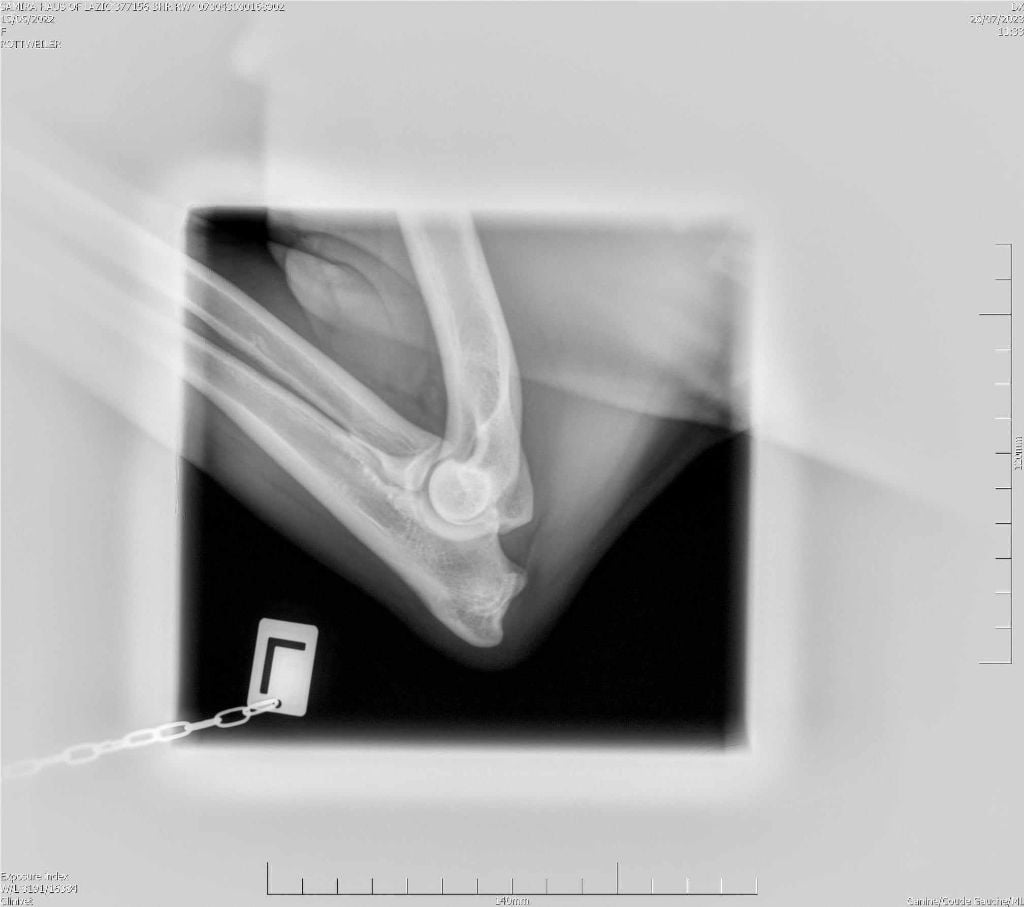

RADIO COUDE OFFICIELLE

COUDE SUITE

ADN : FAIT DYSPLASIE COUDES : ED0 DYSPLASIE HANCHES : HDA JLPP : CLEAR |